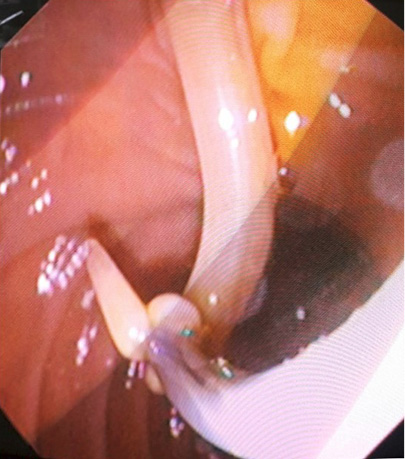

2 pav. Prisipildymo defektas (helmintas) BTL (pažymėta rodykle), nesant echogeninio šešėlio

Atlikus ultragarsinį pilvo tyrimą, konstatuota, kad tulžies pūslė pašalinta, BTL 0,8–1,0 cm pločio. Jo spindyje pastebėtos hiperechogeniškos masės (0,6–0,8 cm skersmens), distaliniame gale susiliejančios į didesnes sankaupas (1, 2 pav.). Kitų vidaus organų ir struktūrų matomų patologinių pokyčių nenustatyta.

Sergant tulžies latakų askaridoze, kraujo tyrimai gali atitikti normos ribas. Tokiu atveju įtarti patologiją padeda paciento nusiskundimai, išsami ligos ir gyvenimo anamnezė (kelionės, namų aplinka, valgymo įpročiai ir sąlytis su dirvožemiu). Specifinių (ligą diagnozuojančių) laboratorinių tyrimų askaridozei nustatyti nėra. Tiksliai diagnozuoti parazitų invaziją į žarnyną, kai laboratoriniai tyrimai nepatologiniai, galima identifikavus askaridžių kiaušinėlius paciento išmatose [3, 27]. Kirmėlių migraciją į tulžies latakus galima nustatyti atlikus ultragarsinį tyrimą. Dažnai ultragarsu pastebimas prisipildymo defektas BTL. Jis būna pailgos arba cirkuliarios formos, be tulžies latakų akmenims būdingo šešėlio – artefakto. Dėl šios priežasties ultragarsu stebimas prisipildymo defektas dar vadinamas „minkštu“ radiniu (1, 2 pav.). Nors ultragarsinis tyrimas vertinamas kaip jautrus ir specifiškas (atitinkamai 40–70 proc. ir 90 proc.), tyrimo kokybė priklauso ir nuo tyrėjo patirties. Tulžies latakuose esant oro po buvusių intervencijų arba kirmėlių maceracijos metu, kai kirmėlė negyva, ji gali būti nepastebėta [2, 3].